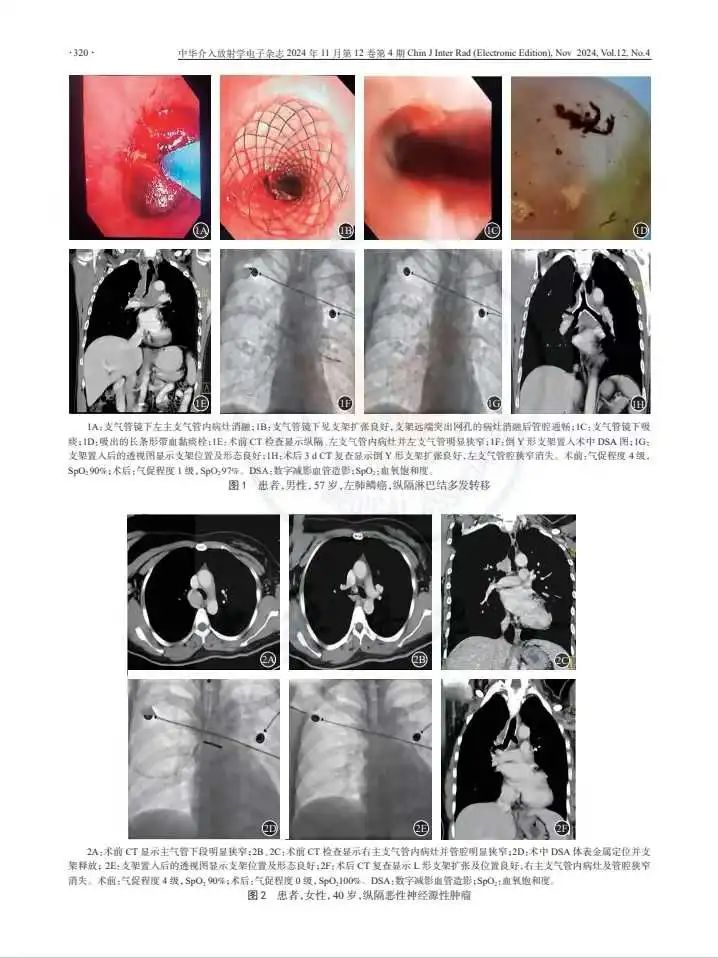

上面这位患者来自巴基斯坦,双肺多发转移病灶,经过化疗、靶向药治疗后仍有部分转移。由于病灶较大,挤压并粘连双侧支气管、左心房、双下肺静脉、胸主动脉、食管,以至于该患者气道复杂、狭窄,呼吸困难。我们介入团队在内镜联合DSA引导下,进行气道内肿瘤消融+支架植入术,反复电切、止血、消融、疏通的同时植入支架,历经近三个小时终于打通了气道,为进一步治疗争取了时间。

常规治疗不能直接解决气道阻塞的症状,外科手术治疗创伤大且不能反复进行。近年来,随着支气管镜介入技术的发展,因其能够避免传统外科手术创伤大、适应症局限、术后吻合口再狭窄等问题,逐渐成为治疗恶性气道狭窄的主要治疗方法。

其中,支架置入是指通过导管将支架送至气管内的狭窄部位,张开后起到支撑管壁,维持气道通畅的作用,从而达到改善呼吸功能的目的,主要针对恶性肿瘤引起的气管支气管狭窄进行姑息治疗,以迅速解除患者呼吸困难的症状,为后续治疗创造条件和机会。

像这位患者因反复咳嗽咳痰,伴胸前区压迫感,在当地医院确诊为肺癌。因邻近食管粘连受侵,形成肿瘤-食管、右侧支气管瘘,气管、右侧支气管局部受压粘连,管腔不均匀变窄,以至于呼吸困难。在我院,我们在DSA引导下在其食管中段狭窄处放置支架,打通生命的“营养快线”。并根据恢复情况,为其实行气管肿瘤射频消融以及支架植入手术,缓解气管阻塞、呼吸困难的症状。术后患者表示,“呼吸畅通,饮食顺畅的感觉简直太好了。”

气道狭窄往往需要根据气道狭窄的部位、狭窄程度,同时结合原发病、全身情况来制定治疗方案,采取镜下多种手段联合治疗,还要联合全身有效的病因治疗,才能取得良好疗效。对于改善生活质量,缩短病程,具有重要意义。

我们介入科团队在这方面有成熟和丰富的诊疗经验。术中麻醉医生全程配合,支气管镜联合DSA在恶性气道狭窄中的活检、吸痰、止血、冷热消融及支架置入,技术成功率100%,安全且疗效满意,为患者点亮生命之光。